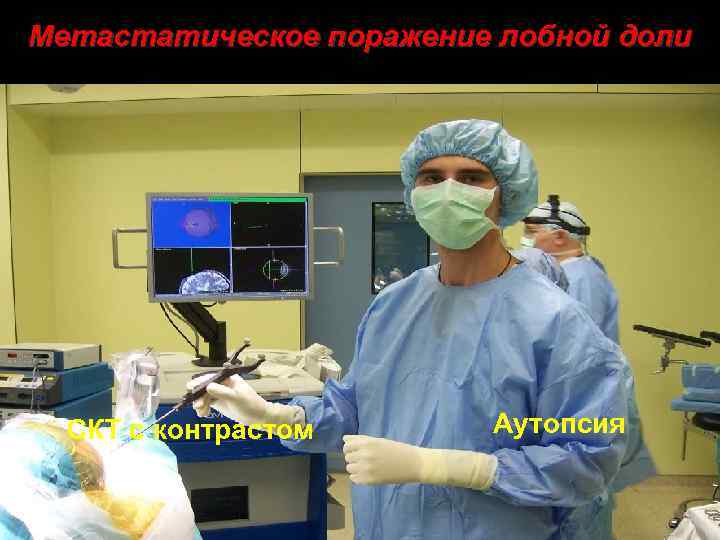

Метастатическое поражение лобной доли СКТ с контрастом Аутопсия 39